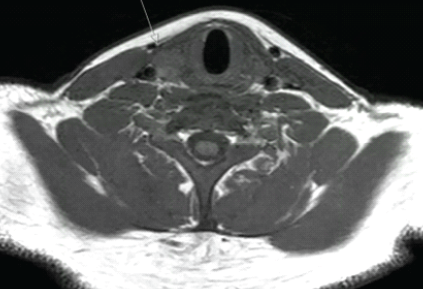

Incidence and Functional Impact of Malrotation after Intramedullary Nailing of Femoral Shaft Fractures: A Prospective Computed Tomography-based Observational Study

Nitish Kumar , Navdeep Singh Keer , Loveneesh G Krishna , Protik Mukherjee , Ishaan Siwach , Balu Ravi